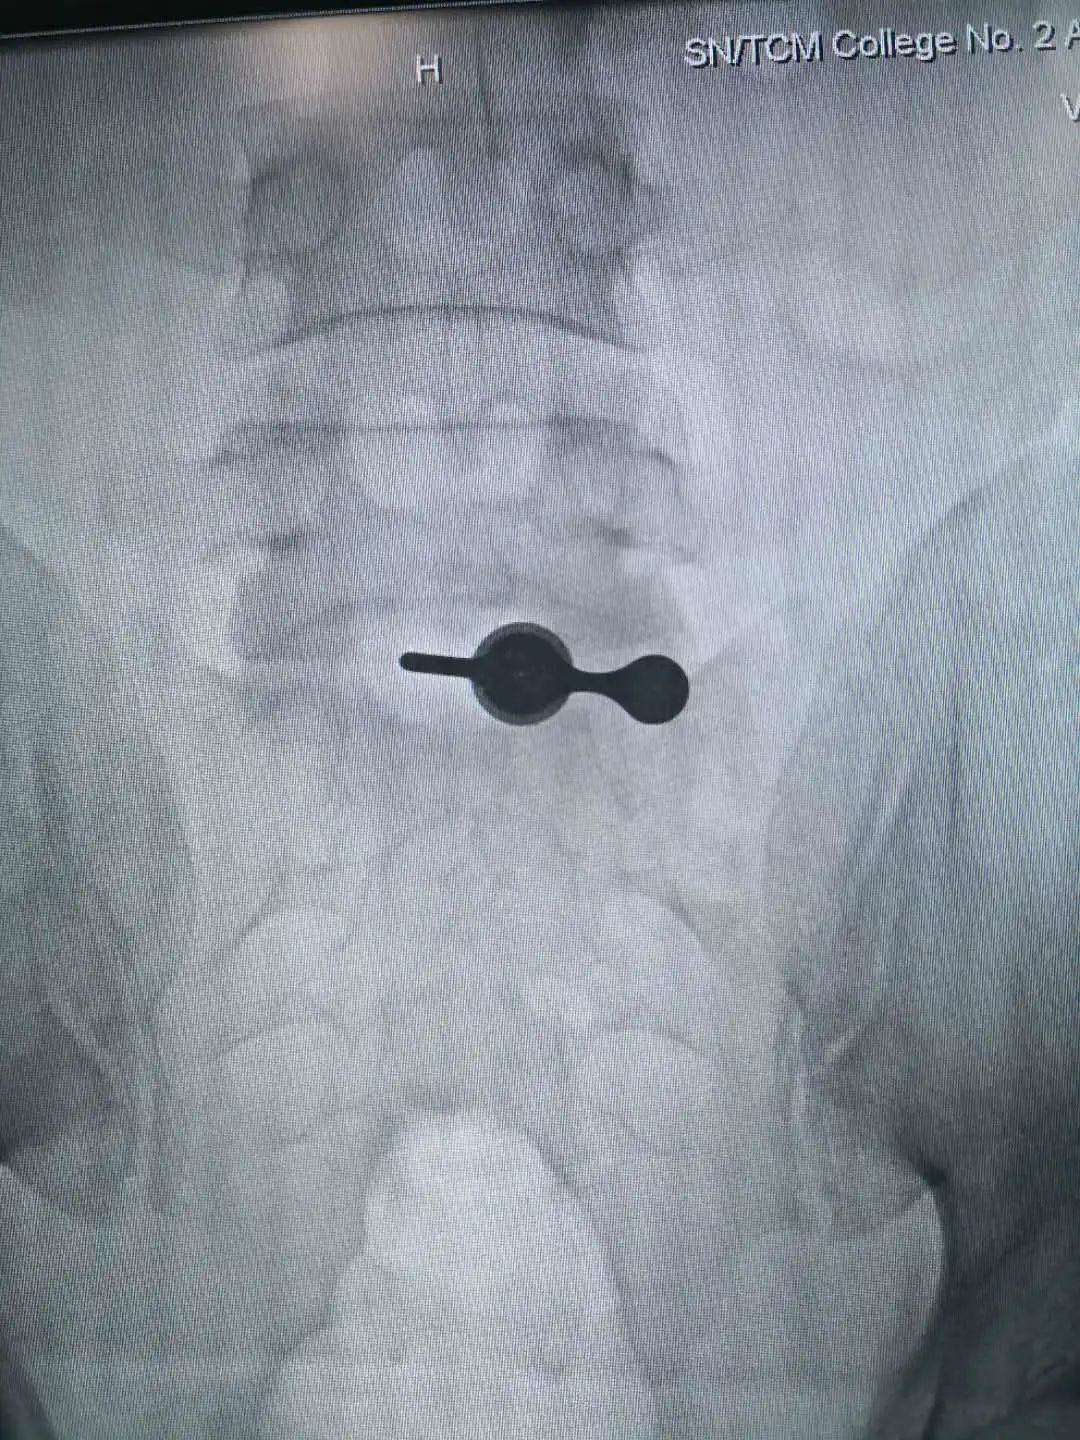

患者入院后,科室给予保守治疗,但症状缓解不明显。医院副院长寇久社、科室副主任张保平及相关医护人员对病情进行多次讨论后,一致认为患者疼痛为腰椎间盘突出神经根受压所致,拟行手术治疗。但患者年纪较轻,家属拒绝进行开放手术。经仔细评估及与患者家属充分沟通后,科室决定对他实施椎板间入路内镜下脱出髓核摘除术。

术前讨论中,科室充分考虑到患者生命体征、年龄及心理等因素,针对手术过程中心、肺、脑等重要脏器可能出现的各种意外,也制定了充分的应急预案。手术顺利完成,术后患者安返病房, VAS疼痛评分稳定在0-1分,当天夜里就可以安静入睡,术后第1天就可以下床行走了,腰腿疼痛明显缓解,生活质量得到很大提高。